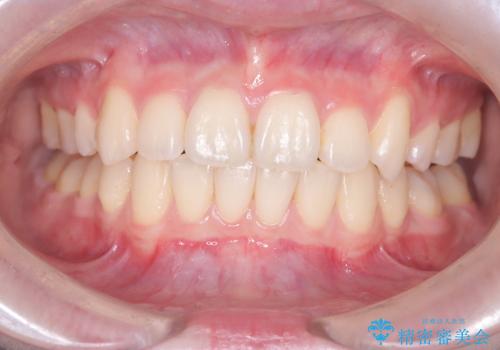

前歯の突出を防ぎながらガタつきを解消。上下左右4番抜歯による審美ワイヤー矯正

担当医 河口智英